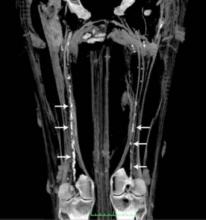

Atherosclerosis is usually considered to be related to contemporary risk factors such as smoking, obesity and lack of exercise. However, researchers suggest that high prevalence of atherosclerosis in pre-modern humans may support the possibility of a more basic human predisposition to the disease.